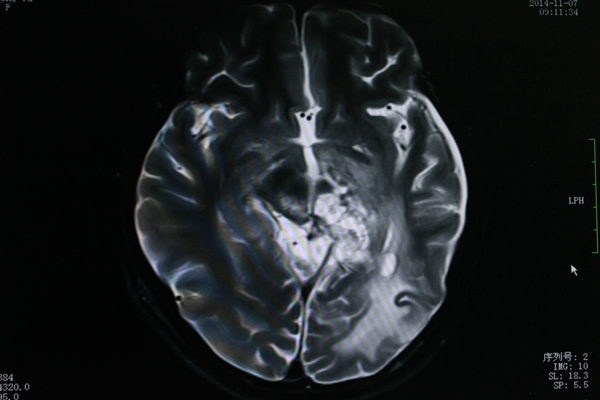

11月MR图像,可见肿瘤已明显缩小。